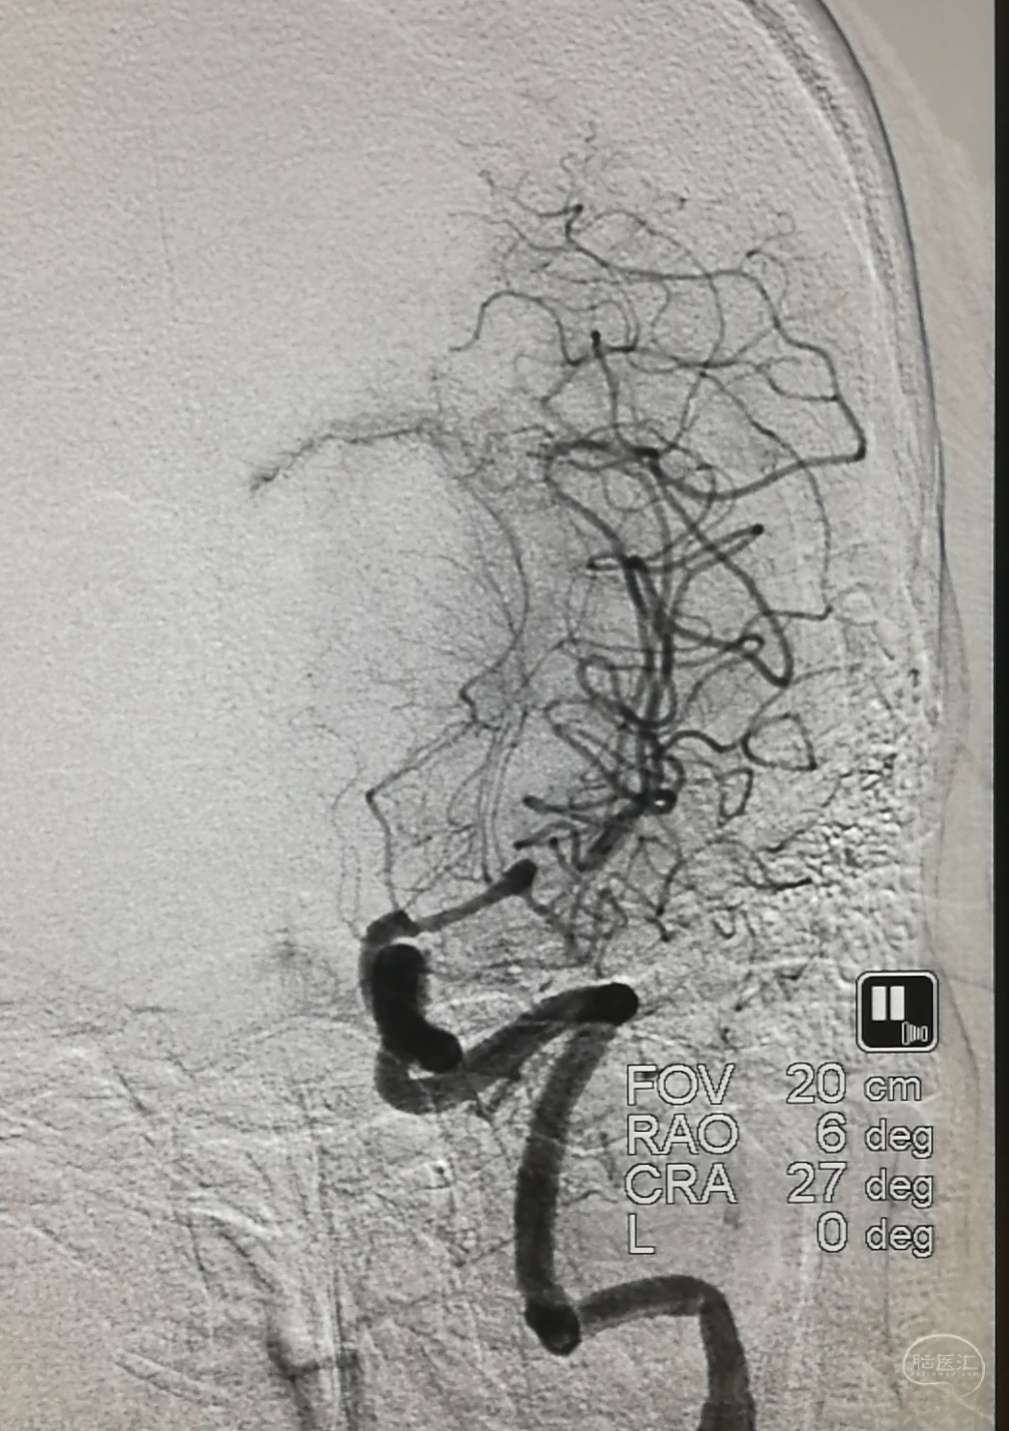

DSA示:左侧大脑中动脉闭塞,烟雾样血管形成。

DSA示颞浅A未向颅内代偿。